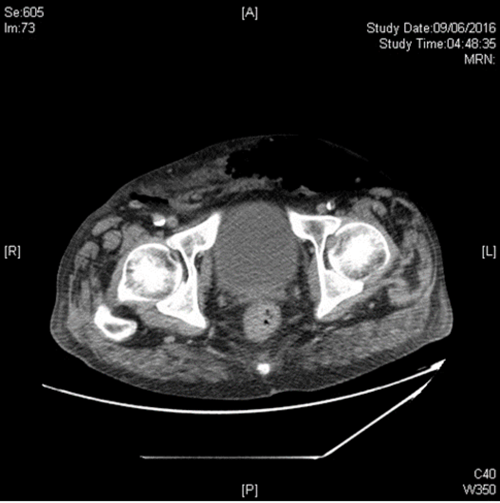

Case 1

An 80-year-old woman presented with history of recurrent and recent cystitis, low grade pyrexia, abdominal and back pain, and pain on movement of the left hip which was observed to be flexed and externally rotated.

- What is the diagnosis from the CT image?

- What are the usual sources of this infection?

- What are the principles of management?

Iliopsoas abscess. The classic triad of back pain, limp and fever may actually be present in only 30% of cases. Many patients have an insidious onset of non-specific symptoms and signs. The flexed and externally rotated hip is a consequence of irritation of the psoas muscle and referred pain from the nerve roots L2, L3 and L4 which supply the psoas muscle [1].

The known origins of secondary spread of infection to the iliac or psoas muscles may be broadly categorised into: a) Gastrointestinal (e.g. Crohn’s disease, diverticulitis, appendicitis, colorectal carcinoma); b) Genitourinary (e.g. urinary tract infections including pyelonephritis, instrumentation); c) Musculoskeletal infection (e.g. vertebral osteomyelitis, septic arthritis, infective sacroilitis); d) Others (endocarditis, trauma, femoral artery catheterisation, etc. Tuberculous infection has been implicated from both haematogenous spread and spread from adjacent TB focus, either skeletal, gastrointestinal or genitourinary).

First-line treatment is broad spectrum antibiotics that cover S. aureus (the most commonly isolated organism on cultures from aspirates). Surgical draining is the traditional treatment of choice with some authors describing quicker recovery after, although percutaneous drainage under imaging guidance is a good alternative. The latter may not be effective when small or multiple / multiloculated abscesses occur, or if access if difficult. A co-existing intra-abdominal disease requiring surgical intervention, such as complex Crohn’s disease or diverticulitis, may also determine which option is chosen. Small abscesses may be successfully treated with antibiotics alone [1].